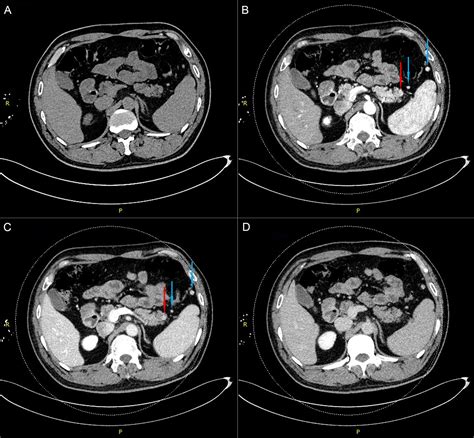

Several diagnostic techniques are used to evaluate the Accessory Pancreatic Duct and its function. These include:

• Endoscopic Retrograde Cholangiopancreatography (ERCP): This procedure involves the insertion of an endoscope into the duodenum to visualize the pancreatic ducts. It allows for the injection of contrast dye to highlight the ducts and identify any obstructions or abnormalities.

• Magnetic Resonance Cholangiopancreatography (MRCP): This non-invasive imaging technique uses magnetic resonance imaging (MRI) to create detailed images of the pancreatic ducts. It is particularly useful for evaluating the Accessory Pancreatic Duct and detecting any blockages or strictures.

• Endoscopic Ultrasound (EUS): This procedure combines endoscopy and ultrasound to provide high-resolution images of the pancreas and its ducts. It is useful for detecting small lesions or cysts that may affect the Accessory Pancreatic Duct.